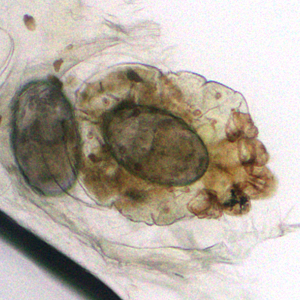

A patient presented to a local hospital with encrusted lesions on his arms and legs. A skin scraping was made and examined unstained at 40x magnification. Figures A and B show what was observed by the attending microbiologist. The images were sent to the DPDx Team for diagnostic assistance. What is your diagnosis? Based on what criteria?

Figure A